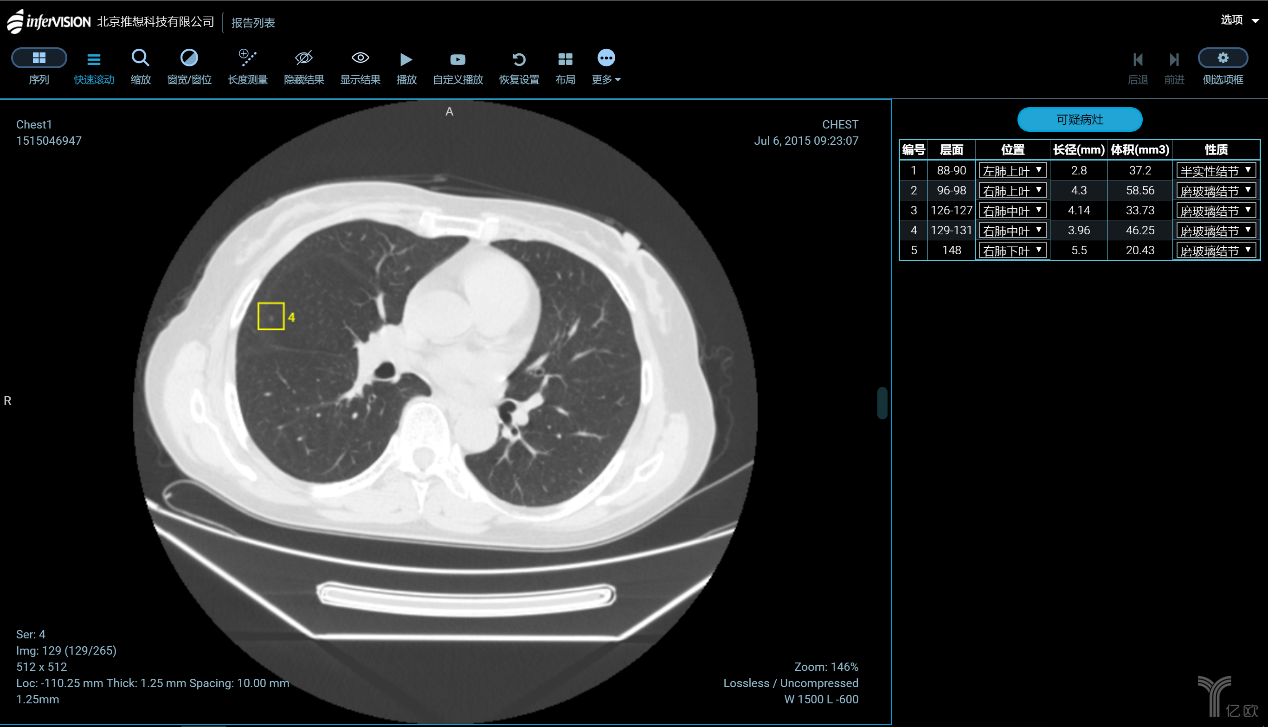

肺結節的識別與診斷,是大部分企業算法模型訓練的起點。一方面是因為中國是肺癌大國,肺部影像數據量最充足;另一方面是由于全球針對肺結節識別的研究最為成熟。國內在肺癌診斷與篩查方向進展較快的,主要有推想科技、圖瑪深維、健培科技、體素科技、依圖醫療、匯醫慧影、深睿醫療、視見醫療、華潤萬里云、零氪科技等。除了肺癌之外,針對乳腺癌、肝癌、鼻咽癌、腦卒中的自動檢測也正在成為焦點。

智能CT輔助篩查產品(AI-CT)功能界面(圖片來源:推想科技)